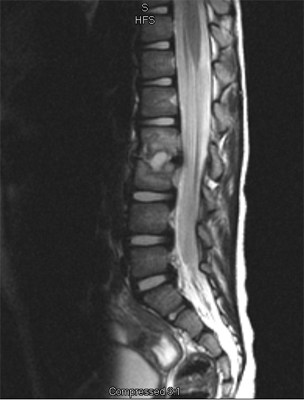

An MRI may be required if further examination of the spine is needed. An MRI machine uses magnetic waves, not X-rays, to show the soft tissues of the body. These tissues include the spinal cord, nerves, and discs. It can also evaluate spinal bones. An MRI allows your healthcare professional to look at slices of the area in question. The test may require the use of dye in an IV. Sedation or anesthesia may be needed to help your child lie still for this test.